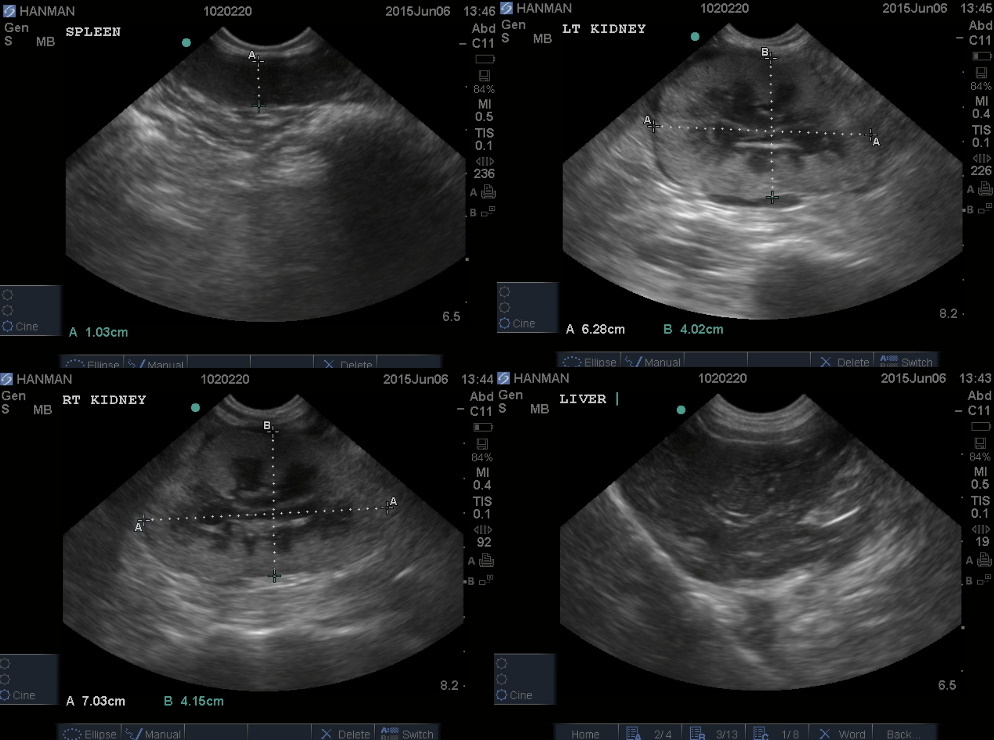

五月中旬憨面坐姿和臥姿感覺腹腔很不舒服

回診檢查腎臟有浸潤的現象,懷疑可能有轉移

腎指數偏高體重一直下降

照片使用的是紀錄